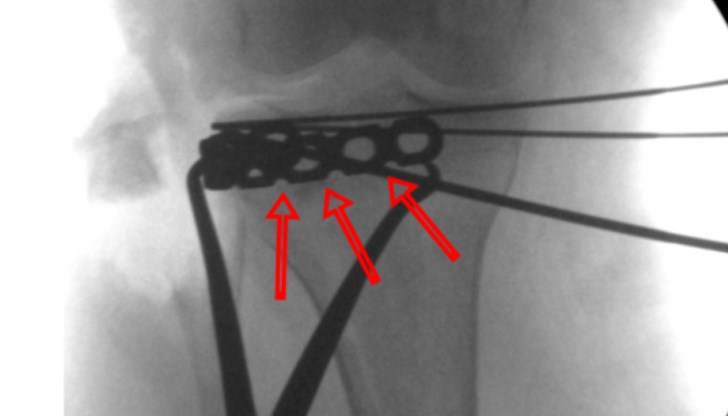

„С кост от таза на пациентката се попълни образувалия се дефект. Иновативното в случая е начинът, по който се фиксира цялата конструкция от присадена кост и фрактура с т. нар. рим плака. Тази плака като корона обхваща горния сегмент на подбедрицата и осигурява разнопосочно прокарване на винтовете, които изпълняват ролята на подпора за постигнатото наместване“, допълни той.

По думите на доц. Андонов хирургия на такъв вид фрактура се прави навсякъде, но на русенския екип не е известно някъде в България да се прави фиксацията по този начин с иновативния имплант. Предимството на метода е, че е лесен и позволява ранно раздвижване на ставата, като скъсява с месеци възстановителния период.